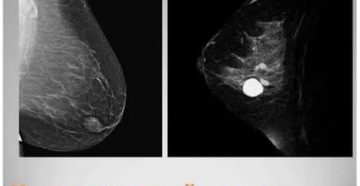

Что можно, а что нельзя при мастопатии: загорать, заниматься спортом и ходить в баню Мастопатия…